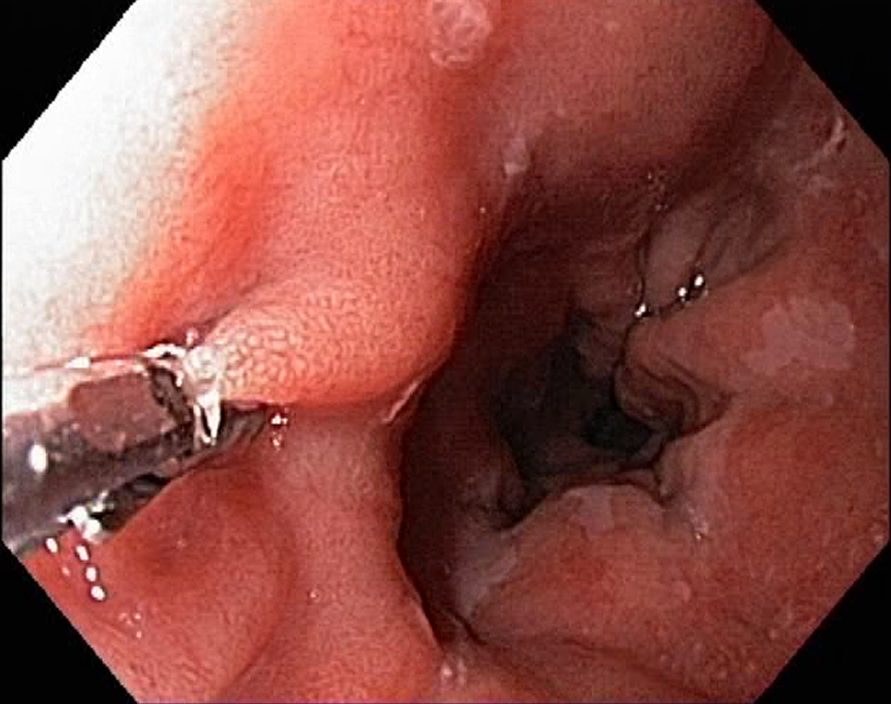

Barrets Oesophagus (NBI, Narrow Band Imaging)